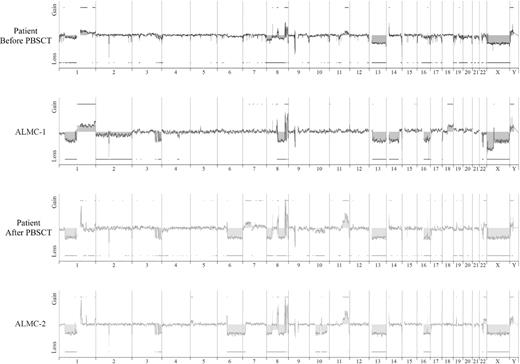

We next used array CGH, a methodology that permits a much higher resolution map of the 4 genomes than that achieved by conventional methods (Figure 4), to test the genetic relationship between the cell lines and the primary patient cells. This analysis permits 2 major conclusions. First, the data clearly demonstrate the overall similarity between the cell lines and the patient primary cells. Second, a number of genetic changes were acquired during the course of disease progression, including regional chromosomal gains in 1q, 11q, and 22q, and losses in 6q, 8p, 10p, and 10q, several of which have been associated with poor prognosis myeloma (reviewed by Tonon30 ). Of interest, 6q deletion is frequently observed in Waldenstrom macroglobulinemia and is associated with features of adverse prognosis.31

Genome-wide high resolution aCGH. Chromosomal copy number alterations across the pre-PBSCT, ALMC-1, post-PBSCT, and ALMC-2 cells are plotted for each probe evenly aligned along the x-axis in chromosomal order.

Although it is beyond the scope of this report to present a detailed analysis of all gains and losses, Figure 5 presents a more detailed view of chromosomes 1, 3, 8, and 22. Chromosome 1q21 is amplified only in the primary patient cells post-PBSCT and the ALMC-2 line. This region has a number of interesting genes that have been shown to play a role in other cancers, including the transcription factor, Arnt32 ; the Bcl2 family member, Mcl133 ; the micro RNA, MIRN55434 ; FLG2, a member of a family of genes whose products interact with intermediate filaments35,36 ; and the DNA-binding histone protein, HIST2H2AB.37 Several regions on chromosome 3 have undergone losses in all 4 samples tested and include ABCC5, a multidrug resistance gene,38 and ATP13A5, a lipid-transporting p-type ATPase.39 The transcription factor, TRMT12 (chromosome 8), has been shown to be amplified in breast carcinoma40 and is amplified in both primary patient samples and both cell lines (Figure 5). Finally, losses were also observed on chromosome 22 in all 4 samples. One of these regions includes the IGL locus and probably reflects genomic DNA lost on chromosome 22 during VJ rearrangement. Consistent with λLC expression, there is a biallelic loss of the κLC locus on chromosome 2p12 in all 4 samples studied (Figure 4). The second region of chromosome 22 loss highlighted involves the NF-2 gene, a known tumor suppressor gene.41,42 Collectively, these data demonstrate how closely the in vitro passaged cell lines resemble the primary patient cells. This analysis also demonstrates how the cell line established from the diagnostic marrow similarly evolved, albeit in vitro, in a way that largely mirrored in vivo evolution of the primary tumor.